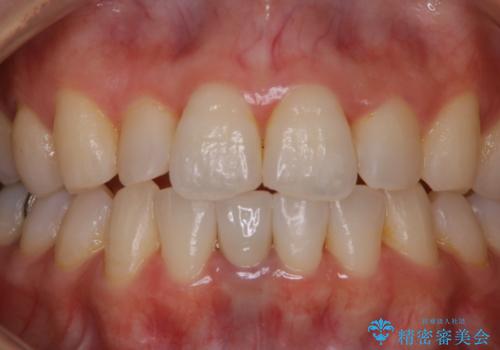

- 夜間の歯ぎしり・食いしばり予防のナイトガードを作成希望とのことで来院されました。しばらくクリーニングも受けていないとのことでPMTC30分コースを行いました。

プラークや歯石により、歯肉が炎症している場合、歯と歯肉の境目が鮮明に型取り出来ないなどがあります。そのため、マウスピースの作成前などには、PMTCで歯の表面の汚れを落とすことで、仕上がりのマウスピースがより精密なものとなります。